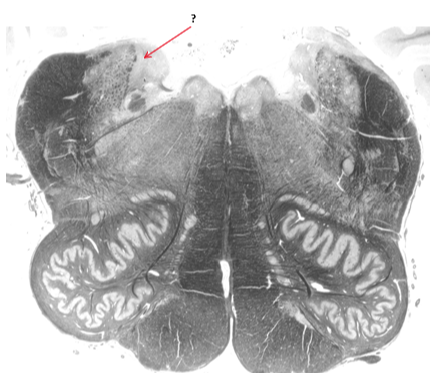

Name this and state its function.

Inferior cerebellar peduncle.